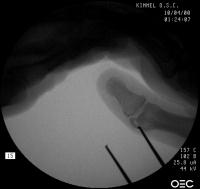

Intraoperative fluoroscopy. The mass:

Click for larger image

Osteotomy planning: proximal pin parallel to the proximal joint line, distal pin parallel to the distal joint line: